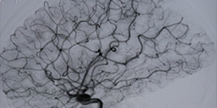

脑动静脉畸形(arteriovenous malformation,AVM)是脑血管发育异常所致畸形中最常见的一种。占脑血管畸形90%以上。畸形血管是由动脉与静脉构成,有的包含动脉瘤与静脉瘤,脑...>>详细